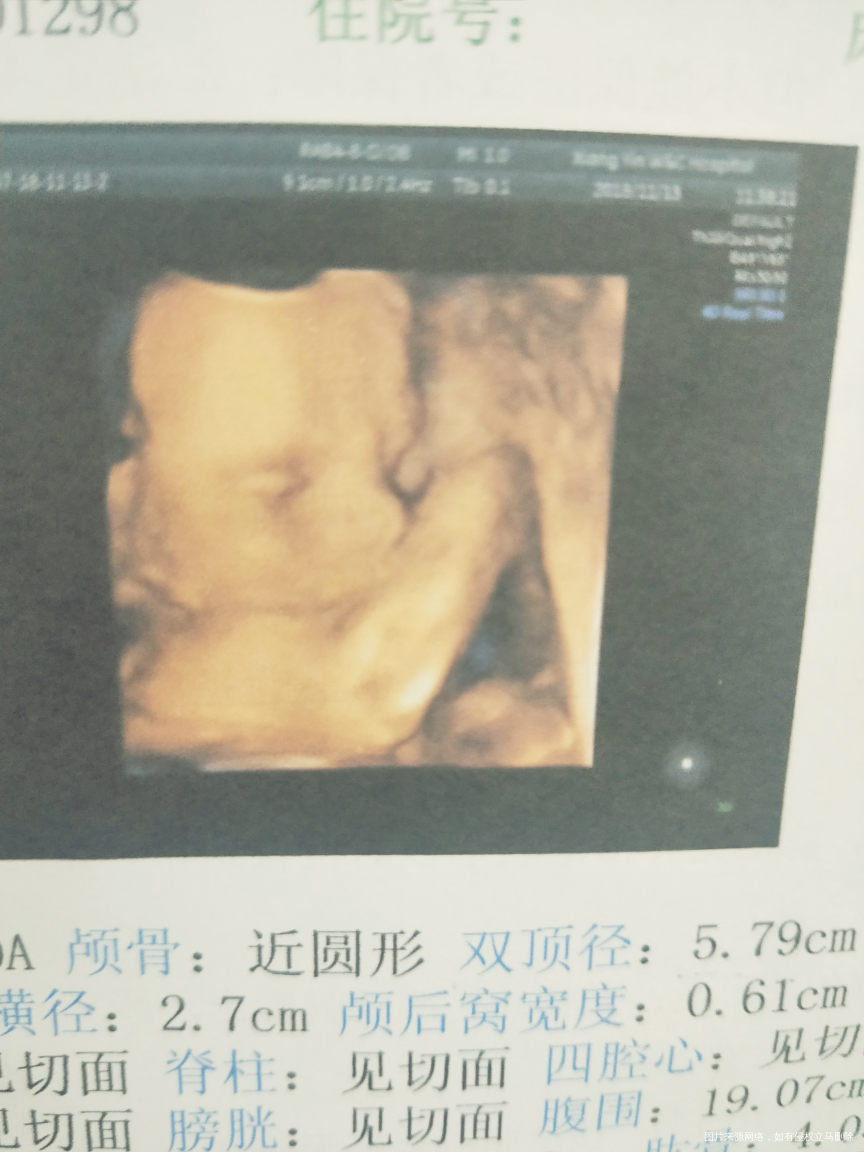

哈哈,时间过的太快,就5个半月了,期待我们宝宝来到我们家!

波波_261422 回复 hyb_1533189303804:我是5个半月去的,